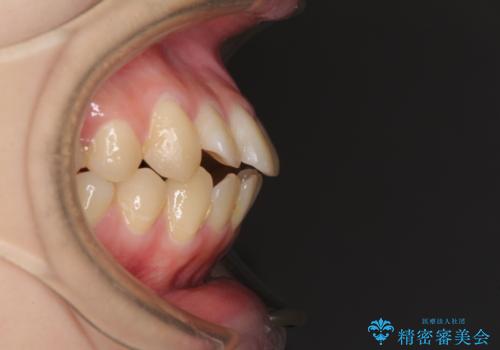

- 上下前歯が前方に飛び出しているとのことで来院された患者様です。

上下左右第一小臼歯4本を抜歯して、積極的に口元を引っ込めるよう、ワイヤー装置にて矯正治療を行うこととしました。

口元の突出感は著しく改善され、横顔の印象が大きく変化しました。